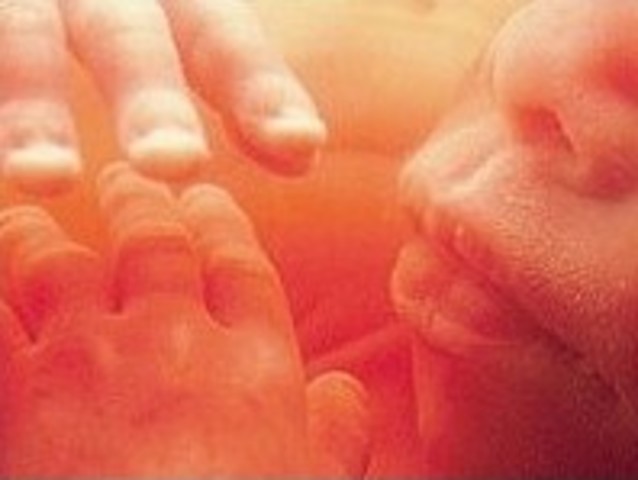

FUN FACT: The fetus' fingernails and toenails are now present.

The fetus' hands are now fully developed and blood vessels within the lungs are developing.

The baby continues to gain weight and beins to cotrol its own temperature. Hands are now fully formed and can grasp things.